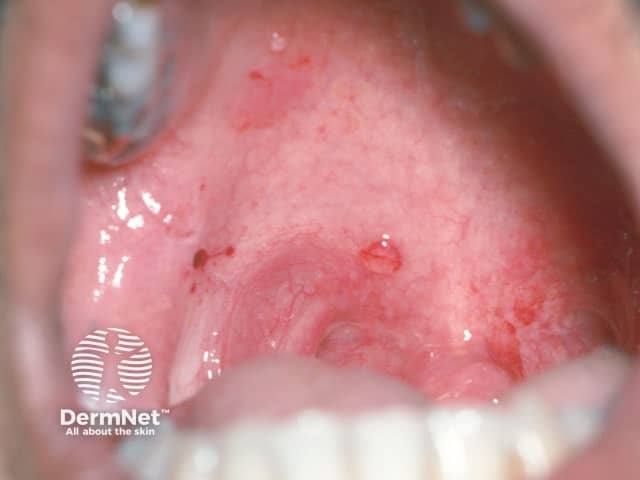

Most patients with pemphigus vulgaris first present with lesions on the mucous membranes such as the mouth and genitals. Blisters usually develop on the skin after a few weeks or months, although in some cases, mucosal lesions may be the only manifestation of the disease.

The inside of the mouth is commonly involved in pemphigus vulgaris. Involvement of the pharynx and larynx cause pain on swallowing and a hoarse voice. Nasal involvement causes congestion and bleeding. The conjunctiva, oesophagus, labia, vagina, cervix, penis, urethra and anus may also be affected.

Features of oral mucosal pemphigus include:

An intact blister on the palate in pemphigus vulgaris